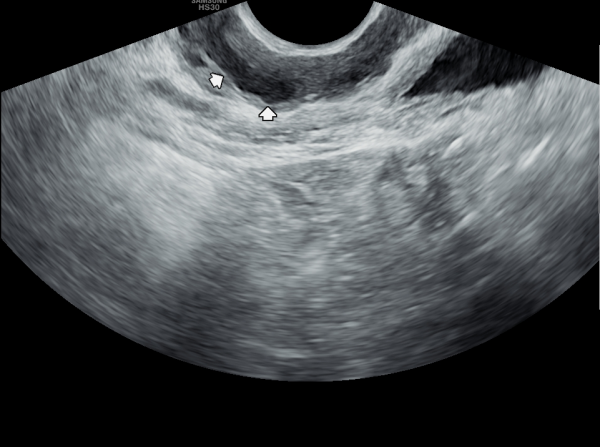

첫 내원 당일 측면 경직장 전립선 초음파 검사상 사정관 입구의 결석과 폐쇄로 사정관 낭종이 관찰되고 사정관에 탈락된 상피세포가 쌓여 사정관이 막히고 있으며 요도 협착등 배뇨 장애로 방관내 조직의 이상 증식이 관찰되는 초음파 사진 입니다.

On the first day of the visit, a lateral transrectal prostate ultrasound revealed stones and obstruction at the entrance of the ejaculatory ducts, leading to ejaculatory duct cysts. Detached epithelial cell debris was observed accumulating and blocking the ducts. In addition, abnormal tissue proliferation within the bladder was noted, likely due to urethral stricture and associated voiding dysfunction.